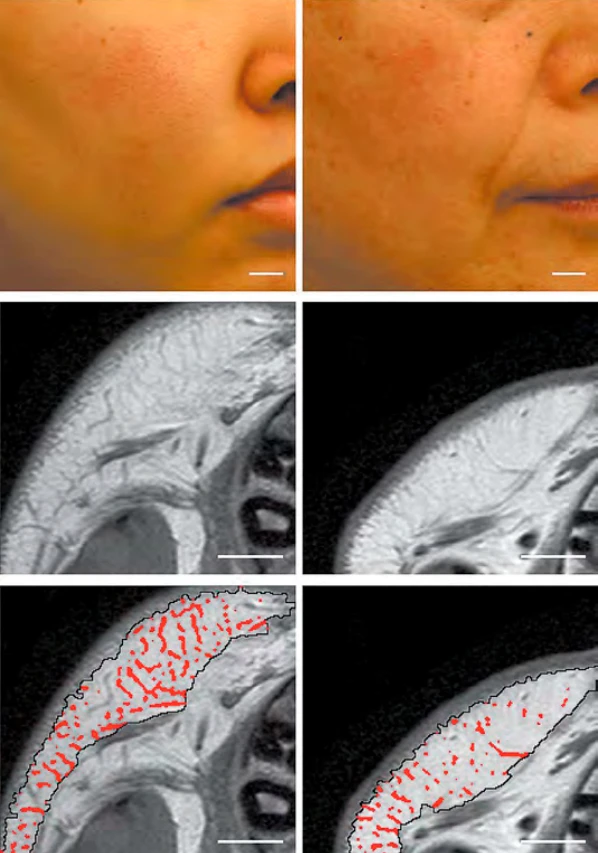

• жировой слой и дерма (образуют фибросептальную сеть, которая разделяет жировую ткань на дольки и затем крепится к дерме, формируя связки кожи retinaculum cutis; RC). RC защищают кожу от гравитации и растяжения, а также сохраняют трехмерную волокнистую структуру (рис. 2)3. С возрастом происходит уменьшение площади и толщины RC, параллельно усугубляется дряблость кожи (рис. 3, 4)4, 5.

Рис. 2. Кожные связки (retinaculum cutis; RC) / фибросептальная сеть жировой ткани (ФСС) передней поверхности предплечья. Белые стрелки – глубокая фасция, черные – RC. М – мышца; Д – дерма3.

...

Рис. 3. Взаимосвязь между дряблостью кожи и площадью retinaculum cutis (RC). Слева – пациент с легкой степенью дряблости кожи; справа – с выраженной дряблостью. Более плотная сеть RC имелась у пациента с менее выраженной дряблостью кожи4.